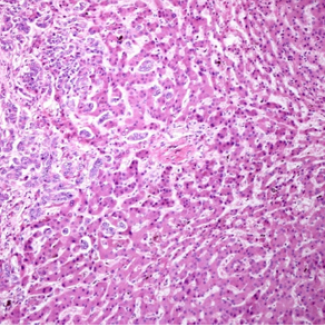

Cancer du pancréas : un anticorps fait ses preuves dans un essai clinique précoce

https://www.cnrs.fr/fr/presse/cancer-du-pancreas-un-anticorps-fait-ses-preuves-…

L’hypusination de eIF5A contrôle la progression du cancer de la prostate

Optimiser la chimiothérapie grâce à des jumeaux numériques

https://www.inc.cnrs.fr/fr/cnrsinfo/optimiser-la-chimiotherapie-grace-des-jumea…